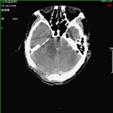

1).硬膜外血肿 术前 术后

2).颅后窝血肿术前 术后